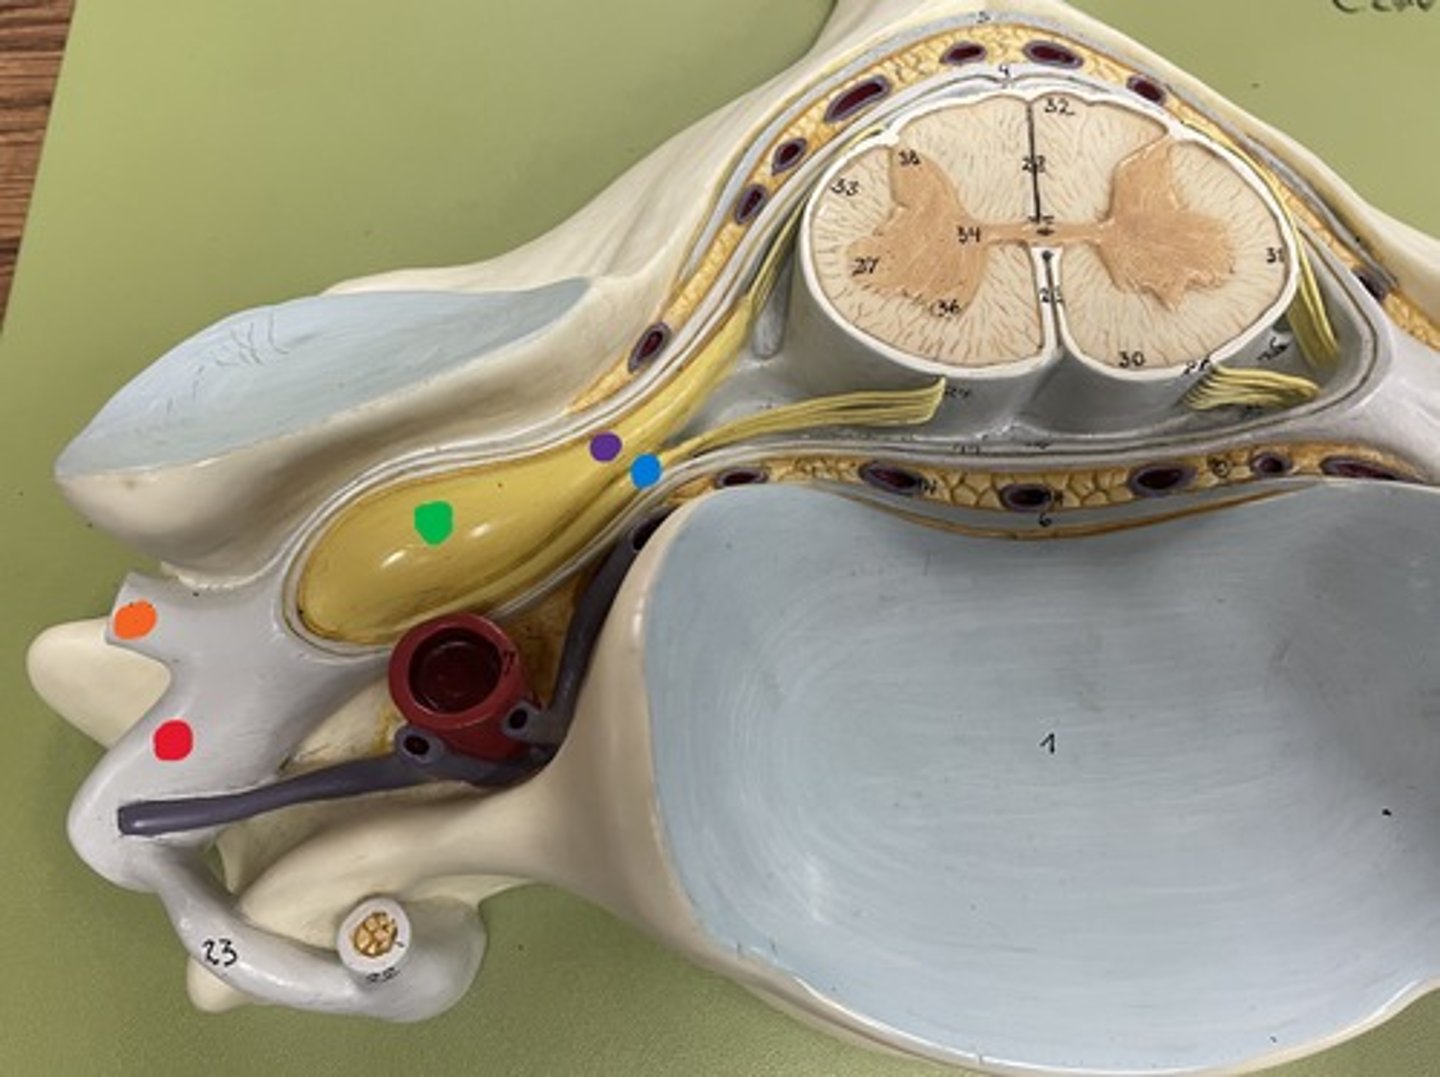

Cervical enlargement

Blue

Lumbar enlargement

Purple

Conus medullaris

Green

Cauda equina

Red

Filum terminale

blue

Epidural space

purple

Subdural space

between red and blue

Subarachnoid space

between red and green

Posterior root

purple

Posterior root ganglion

green

Posterior ramus

orange

Anterior root

blue

Anterior ramus

red